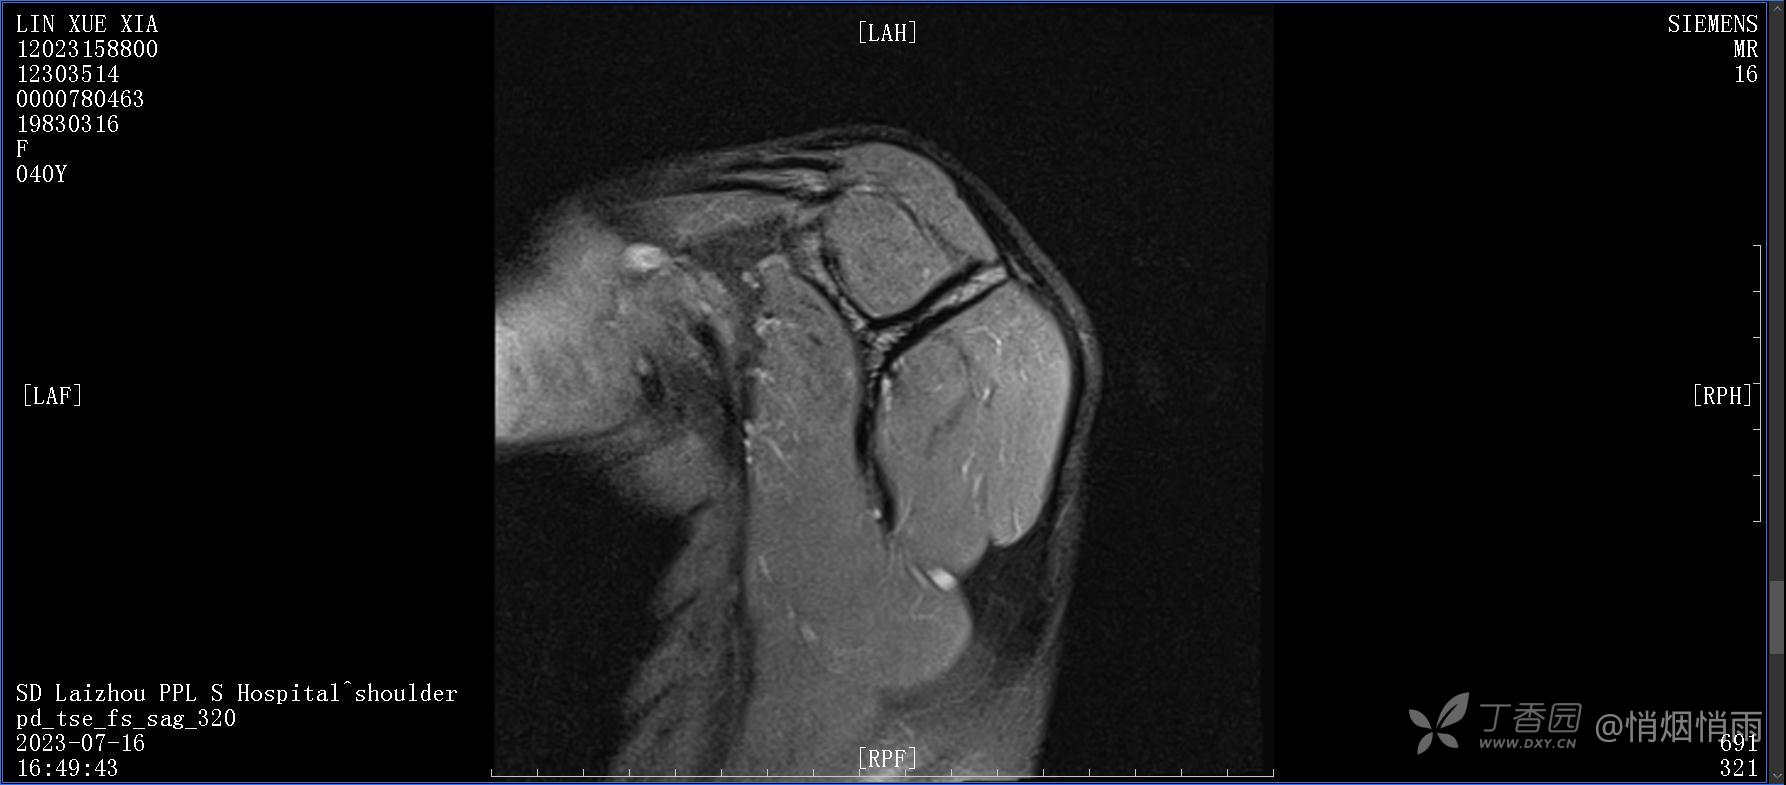

查体:右肩关节局部轻度肿胀,肩胛区压痛明显,痛处不固定,肩关节痛性活动受限,jobe test(+),lift -off test(+),中指、环指感觉较余指减退,余肢端感觉及血运情况可。

目前的诊断,暂时依据辅助检查诊为肩袖损伤,但是患者疼痛的性质和特点,却不是单纯的肩袖损伤所致。考虑过胸廓出口综合征,但是该疾病会出现肩胛区的疼痛吗?(由于考虑到费用的问题,没再进行下一步的检查)带状疱疹会有如此的症状吗?